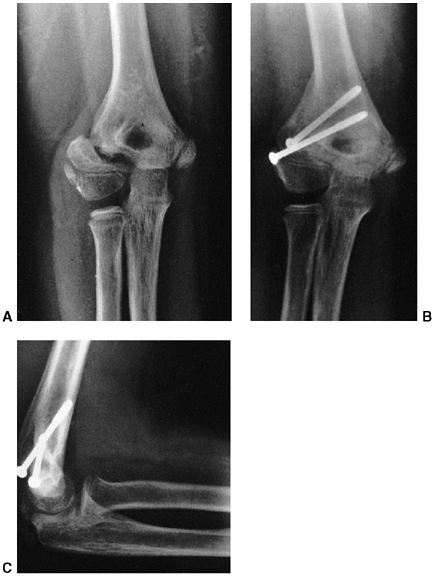

![]() |

|

Figure 33.17 Type II supracondylar humerus fracture with medial impaction and varus alignment. A, B:

Anteroposterior and lateral views of a type II supracondylar humerus fracture with medial impaction. Note that although there is little displacement on the lateral view, the Baumann angle is 0 degrees on the anteroposterior. C, D: Anteroposterior and lateral intraoperative views of the distal humerus after the impacted fracture was reduced and fixed with divergent lateral pins. Note that on the anteroposterior, the Baumann angle is restored, and on the lateral, the anterior humeral line intersects the capitellum. The reduction was maintained during the postoperative period. |